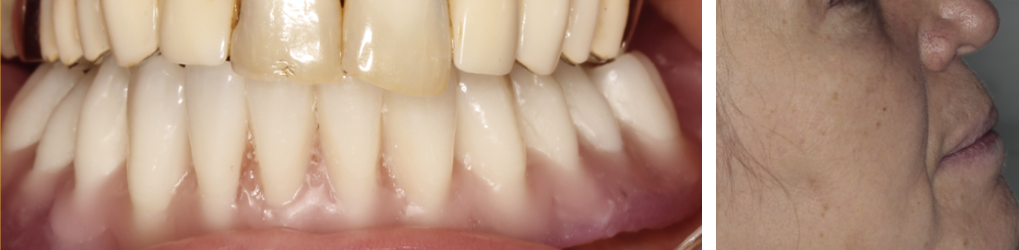

Mai întâi se realizează bara (Fig. 3.9.10) peste care se va aplica viitoarea lucrare. Apoi se realizează o machetă a lucrării pentru a analiza corectitudinea ocluziei (mușcăturii) (Fig. 3.9.11) precum și înălțimea dinților și aspectul facial al pacientului (Fig. 3.9.12, și Fig. 3.9.13).

Aspectul lucrării este unul natural, aceasta îmbunătățind estetica generală și fizionomia pacientului prin redarea conturului feței și plenitudinii obrajilor și a buzelor. Refacerea funcției masticatorii și redarea fizionomiei va aduce o îmbunătățire semnificativă a calității vieții pacienților care aleg acest tip de tratament (Fig. 3.9.15).